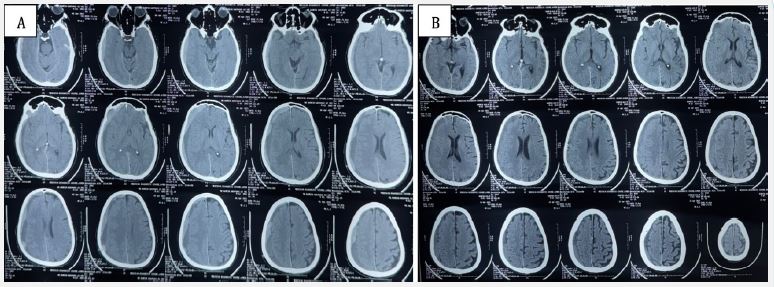

Two weeks later, the patient re-presented with acute-onset holocranial headache for 5 days, severe and non-responsive to analgesics. Repeat NCCT head showed recurrent subacute SDH with acute elements along the same right convexity (Figure 2A). There was no fresh trauma. Given the recurrence and cardiac comorbidity, he was referred to interventional neuroradiology, and underwent middle meningeal artery embolization (MMAE) on April 8, 2025.

The procedure was uneventful, and the patient remained neurologically stable postoperatively with no new deficits. On April 22, 2025, follow-up NCCT showed partial resolution of the hematoma with no fresh bleed (Figure 2B). The patient was asymptomatic and neurologically intact.